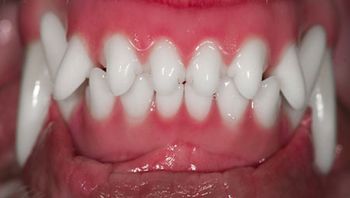

In veterinary medicine, the goal of orthodontic correction isnt a pretty smile but pain-free, functional occlusion.